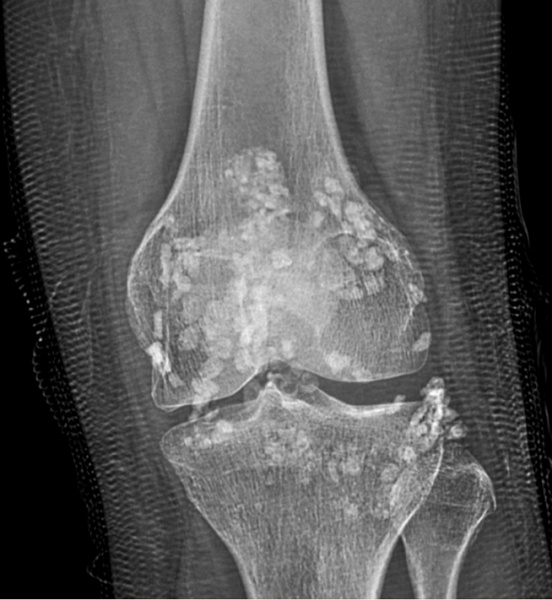

Chụp X-quang cho hình ảnh dưới đây.

Chúng tôi nghĩ đến bệnh Synovial Osteochondromatosis một loại bệnh hiếm gặp và cho bệnh chân chụp MRI khớp cho kết quả sau: